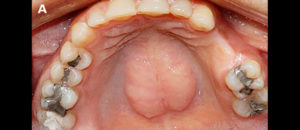

El torus palatino (TP) es una exostosis generalmente asintomática que ocurre comúnmente en la línea media del paladar duro. Su etiología aún no está plenamente